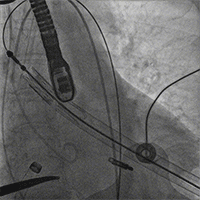

主动脉根部造影后,介入器跨瓣:

定位件进入窦部:

将瓣膜件降至合适水平面:

释放瓣膜后,复查根部造影,未见明显反流,瓣膜形态和位置满意,双侧冠脉显影良好: